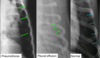

Q

Same animal in both pics.

● Expiration

– Cardiac silhouette appears larger

– Cranial and caudal margin less

defined